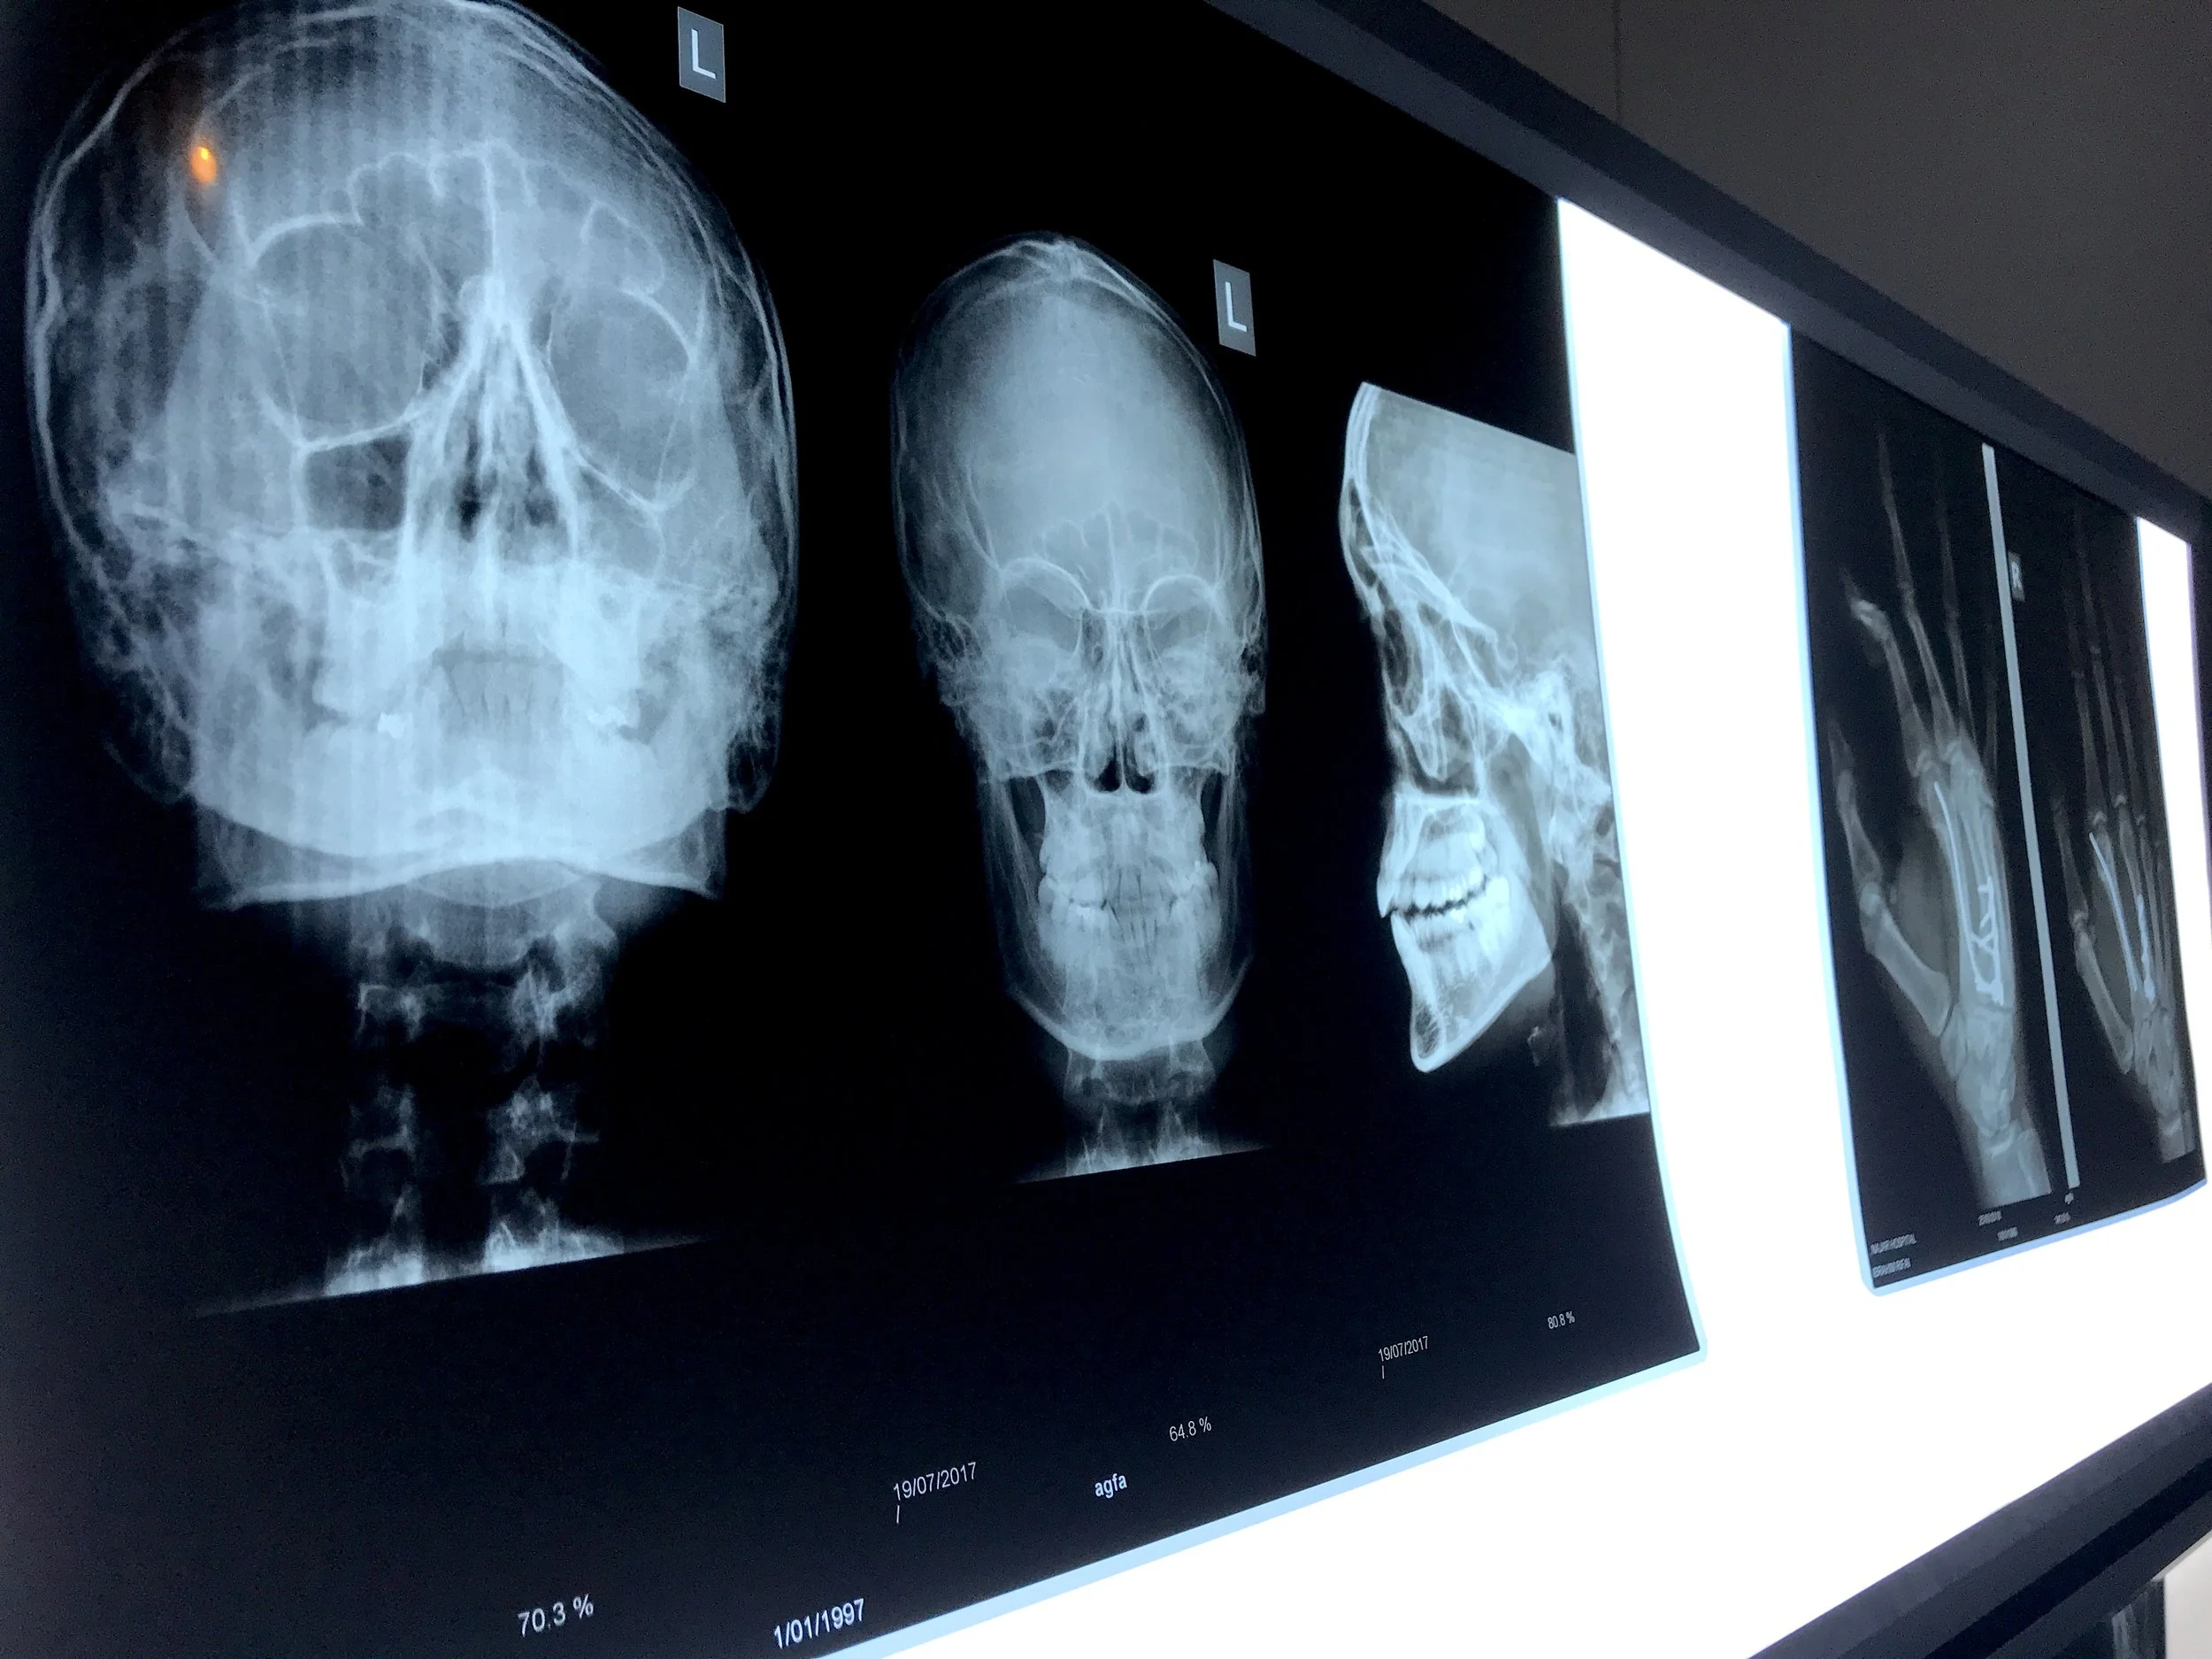

Diagnostic Imaging/Radiology

The Radiology department at Najjar Hospital provides a high standard of imaging services to fulfill the needs of patients. This service is offered by highly specialized radiologists who offer a wide scope of diagnostic services ranging from the most basic to the latest procedures.

General Radiology and Fluoroscopy